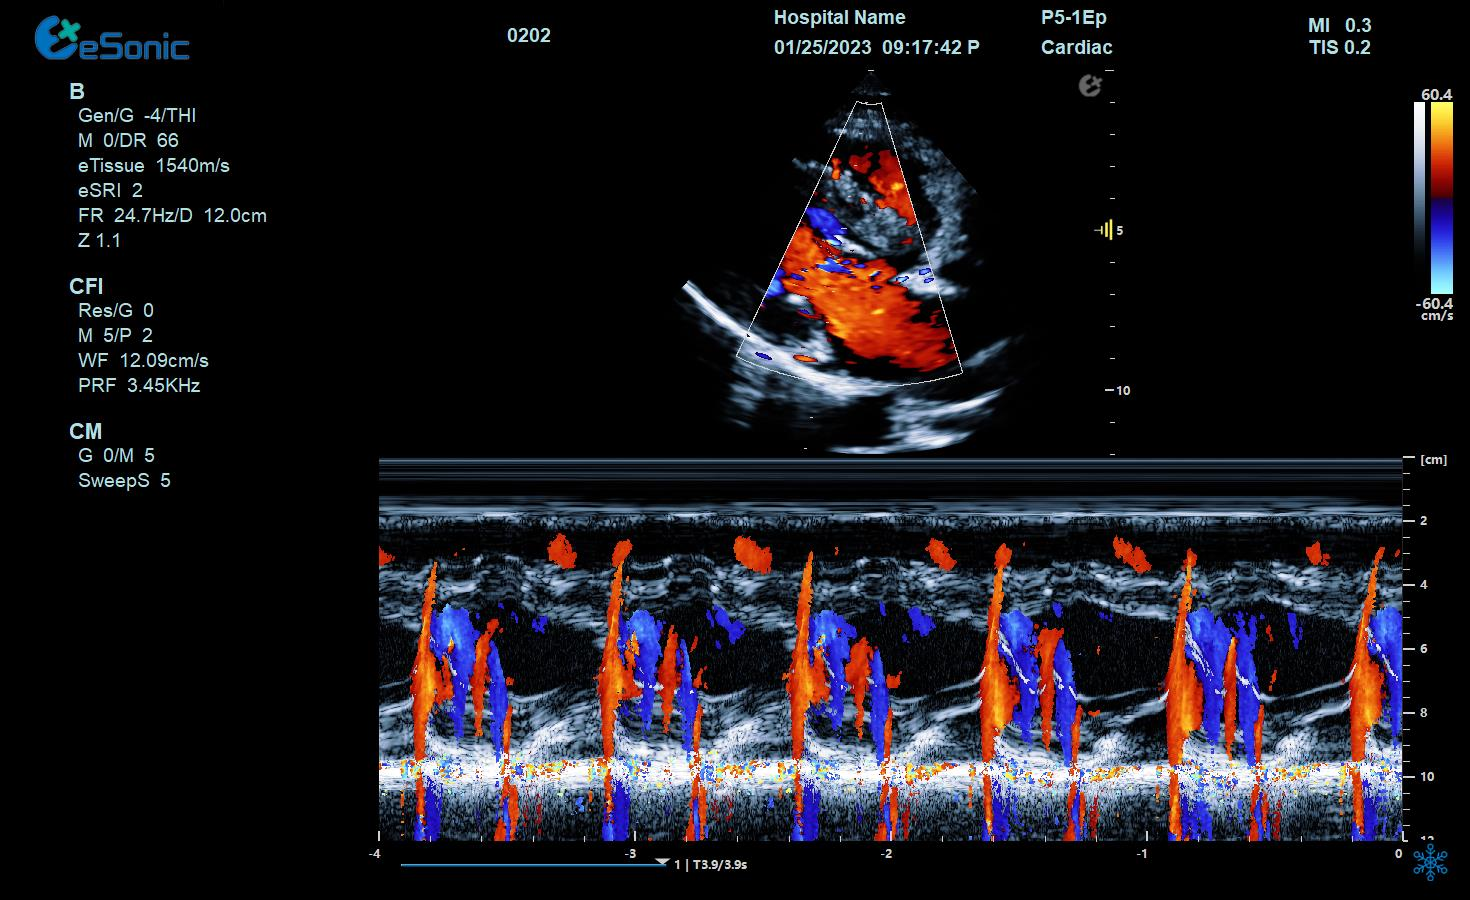

临床病例(二)

男性,82岁,临床诊断:风心病 房颤

超声表现:左房大,二尖瓣增厚、回声增强、运动僵硬;CDFI显示二尖瓣、三尖瓣、主动脉瓣返流信号。

风心瓣膜病二、三尖瓣关闭不全

彩色M型:

直观显示室璧运动和血流动力学关系。

更精准判断血流时向,更精准评估心脏功能。

相关技术优势:eHertz的高敏感血流,提高血流敏感性,降低噪声干扰

eHertz优异的TDI表现- 图像非常干净